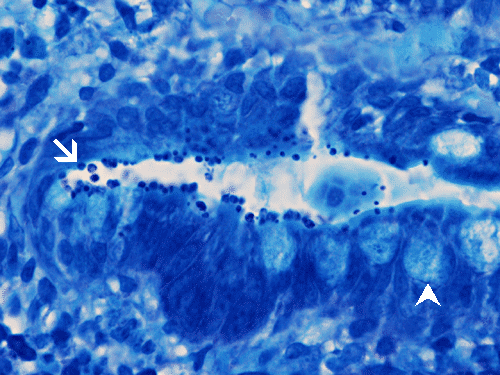

The mucosa is essentially quite normal other than some mild villus blunting in this case. There is no  abnormal inflammatory cell infiltration. However, small bead-like organisms are lining the epithelial surface (arrows in Panel A and B). With Giemsa stain, these microorganisms are positive (arrow in Panel C) and mucin droplets are negative (arrow head in Panel C).These organisms are positive for Giemsa stain. In reality, these small organisms can be identified using medium (10X) magnification if you have a high index of suspicion.

Histologically, two salient features for diagnosis of Cryptosporidium parvum are the characteristic 2 to 5 μm, mostly extracellular, basophilic bead-like spherical bodies that typically line the surface of the intestinal epithelial cells. Cryptosporidium can be found on the surface or the crypts of the small intestine. Giemsa stain is helpful in highlighting these organisms. The mucosa may have other changes including mixed acute and chronic inflammatory cell infiltration, crypt abscess formation,  villous atrophy and crypt hyperplasia. With a high index of suspicion and knowing the clinical history, Cryptosporidium can be picked up easily on medium (10X) magnification and confirmed on higher magnification. Confirmation by immunohistochemistry is helpful.